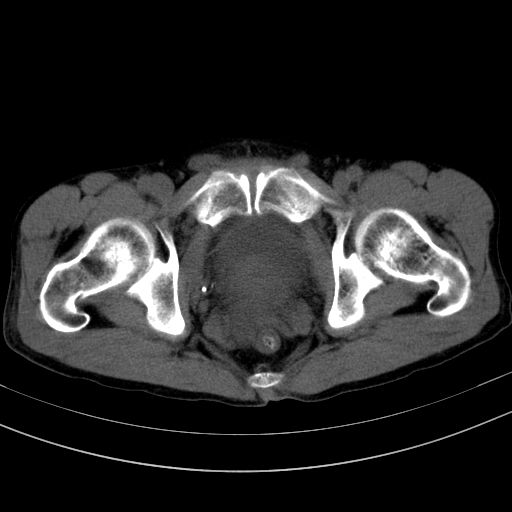

以下是引用37度在2010-1-9 14:37:00的发言:[br]1.双肾囊肿,左肾积水结石,.胆总管轻度扩张;[br]2.病灶在腹膜外,考虑纤维瘤。

以下是引用dyqct在2010-1-9 17:56:00的发言:[br]考虑:1.双肾囊肿,左肾积水结石、旋转不良。[br] 2.右侧腹直肌血肿或纤维瘤。[br]肠道准备不好。做个增强。